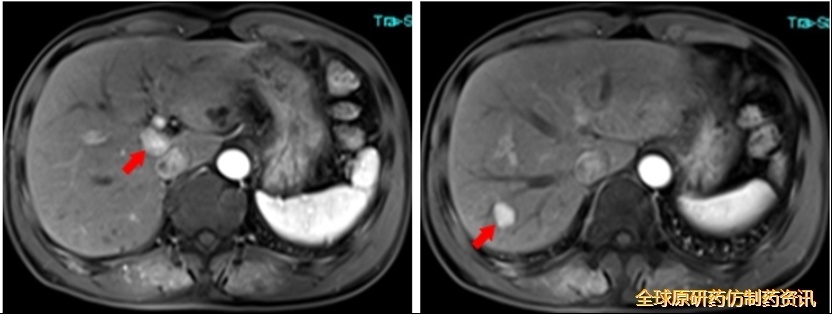

MRI检查:

图1 MRI检查结果

PET/CT检查:

Ⅸb段、Ⅶ段低密度结节,部分代谢增高,考虑HCC,肝外未见转移。

图2 PET/CT检查结果